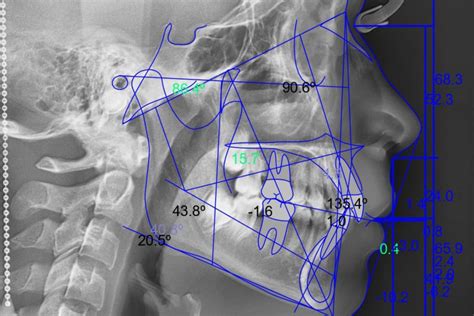

El trazado cefalométrico en ortodoncia se realiza mediante una radiografía lateral de cráneo o telerradiografía. Robert Murray Ricketts (5 de mayo de 1920 - 17 de junio de 2003) fue un pionero en este campo. Su análisis cefalométrico ofrece numerosas ventajas y cualidades que lo hacen una herramienta valiosa en la práctica ortodóncica.

La radiografía es bidimensional, para medirla necesitamos dos ejes que representen los planos cartesianos.

Para realizar un análisis cefalométrico completo, es necesario identificar y trazar varios planos de referencia:

- Frankfort horizontal

- Vertical pterigoidea

- Plano Mandibular

- Plano Facial

- Eje facial

- Plano Basión-Nasión

- Plano Oclusal

- Plano Palatino

- Plano A-Pg

- Plano Estético

- Eje axial de incisivos